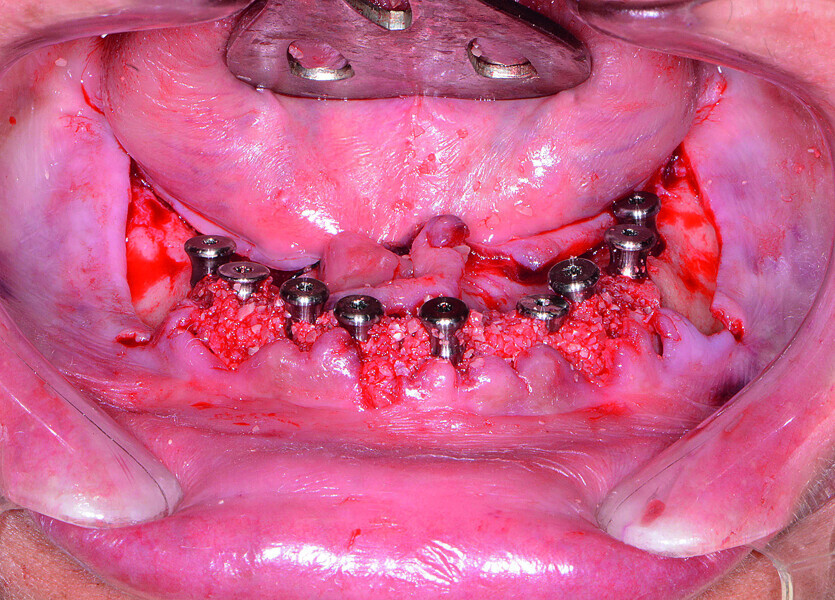

Fig. 15: Implants and healing caps with surrounding grafting.